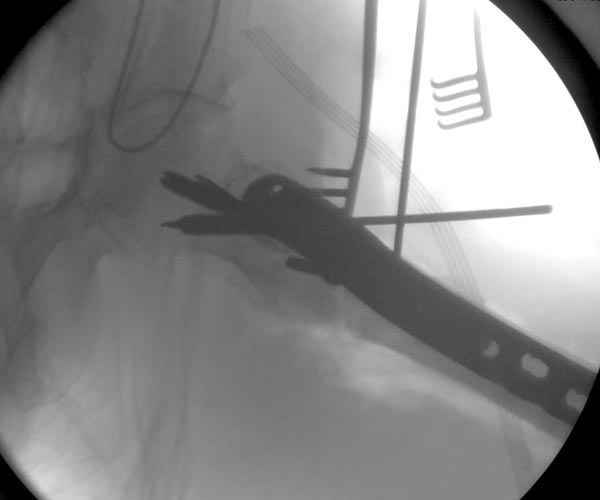

Предугадать распространение линий перелома при чрезвертельных и оскольчатых переломах трудно, поэтому для принятия правильного решения рекомендуется Компьютерно Томографические исследование.

При отсутствии КТ, снимок на вытяжении поможет увидеть общую картину расположения отломков, особенно потенциальные места введения импланта. Риск раскола в этом случае огромный, поэтому больной должен быть дообследован.

А так для лечения оскольчатых переломов подходят все методы, включая интра- и экстрамедуллярные в зависимости от опыта и наличия импланта.

Здесь пара похожих случаев.